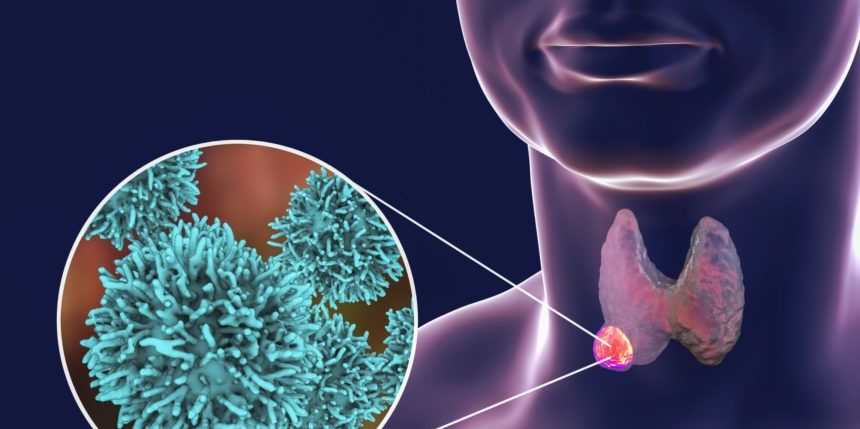

Tiroid kanseri, tiroit bezindeki hücrelerden köken alan bir kanser türüdür. Hastalık kendini çoğu kez boyunda bir kitle belli eder ya da tiroit bezi içinde bir nodül olarak görülür. Tiroit bezi içinde bezelye ya da ceviz büyüklüğünde olabilen ve hücrelerin toplanarak bir araya gelmesi sonucu oluşan topluluğa nodül adı verilir. Nodül hormon üretiyorsa sıcak nodül, üretmiyorsa…